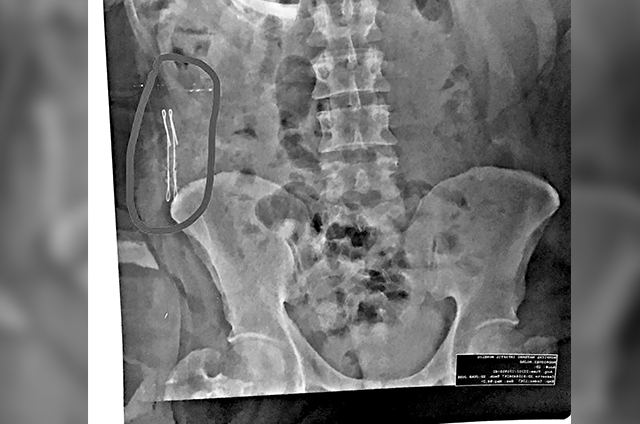

Sin embargo, en lo que parece ser otro caso de negligencia médica por parte del Hospital General, familiares señalan que al practicarle una angiotomografía se detectó “un cuerpo extraño” que en principio se pensó se trataba de una gasa o malla, pero en una nueva imagen pudiera tratarse de otro objeto, incluso piensan alambres.

“Se realiza AngioTac donde se observa en región lumbar, arteria intercostal posterior, con salida de material hemático músculos de la pared posterior izquierda, observándose hematoma desde región lumbar izquierda hasta la cara anterior del abdomen”, agrega el informe. Entre las posibles complicaciones, incluso se encuentra la muerte, concluyen.

Así, el pasado miércoles se trasladó al Hospital General de Chetumal donde le realizaron otra angiotomografía contrastada y sin contraste. Pero el especialista dio una opinión diferente. De entrada detectó que había un cuerpo extraño que podría ser un textiloma y por ende, “ya no le correspondía verlo a él, según los familiares de Ronald. (FERNANDO MORCILLO/GRUPO CANTÓN)